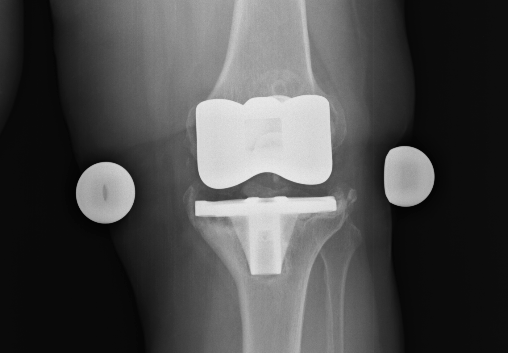

Le protesi al ginocchio utilizzate per la revisione sono, di solito, leggermente diverse da quelle usate nei primi interventi. Infatti, molto spesso le componenti per il femore e per la tibia presentano dei componenti più lunghi, che servono a fissarle meglio all’ osso. Talvolta, viene fatto uso anche di fili metallici, viti etc